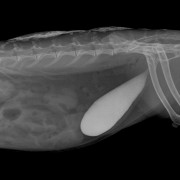

Op de röntgenfoto van de buik worden, afgezien van het beeld van uitdroging, geen afwijkingen gevonden. Omdat Nila veel drinkt wordt ook een uitgebreid bloedonderzoek gedaan. En daar ontdekten we een even verrassende als zeldzame aandoening waar Nila aan leed: Nila heeft de ziekte van Addison. Een aandoening waarbij vrij plotseling de bijnieren uitvallen met een ernstige zieke patiënt tot gevolg.